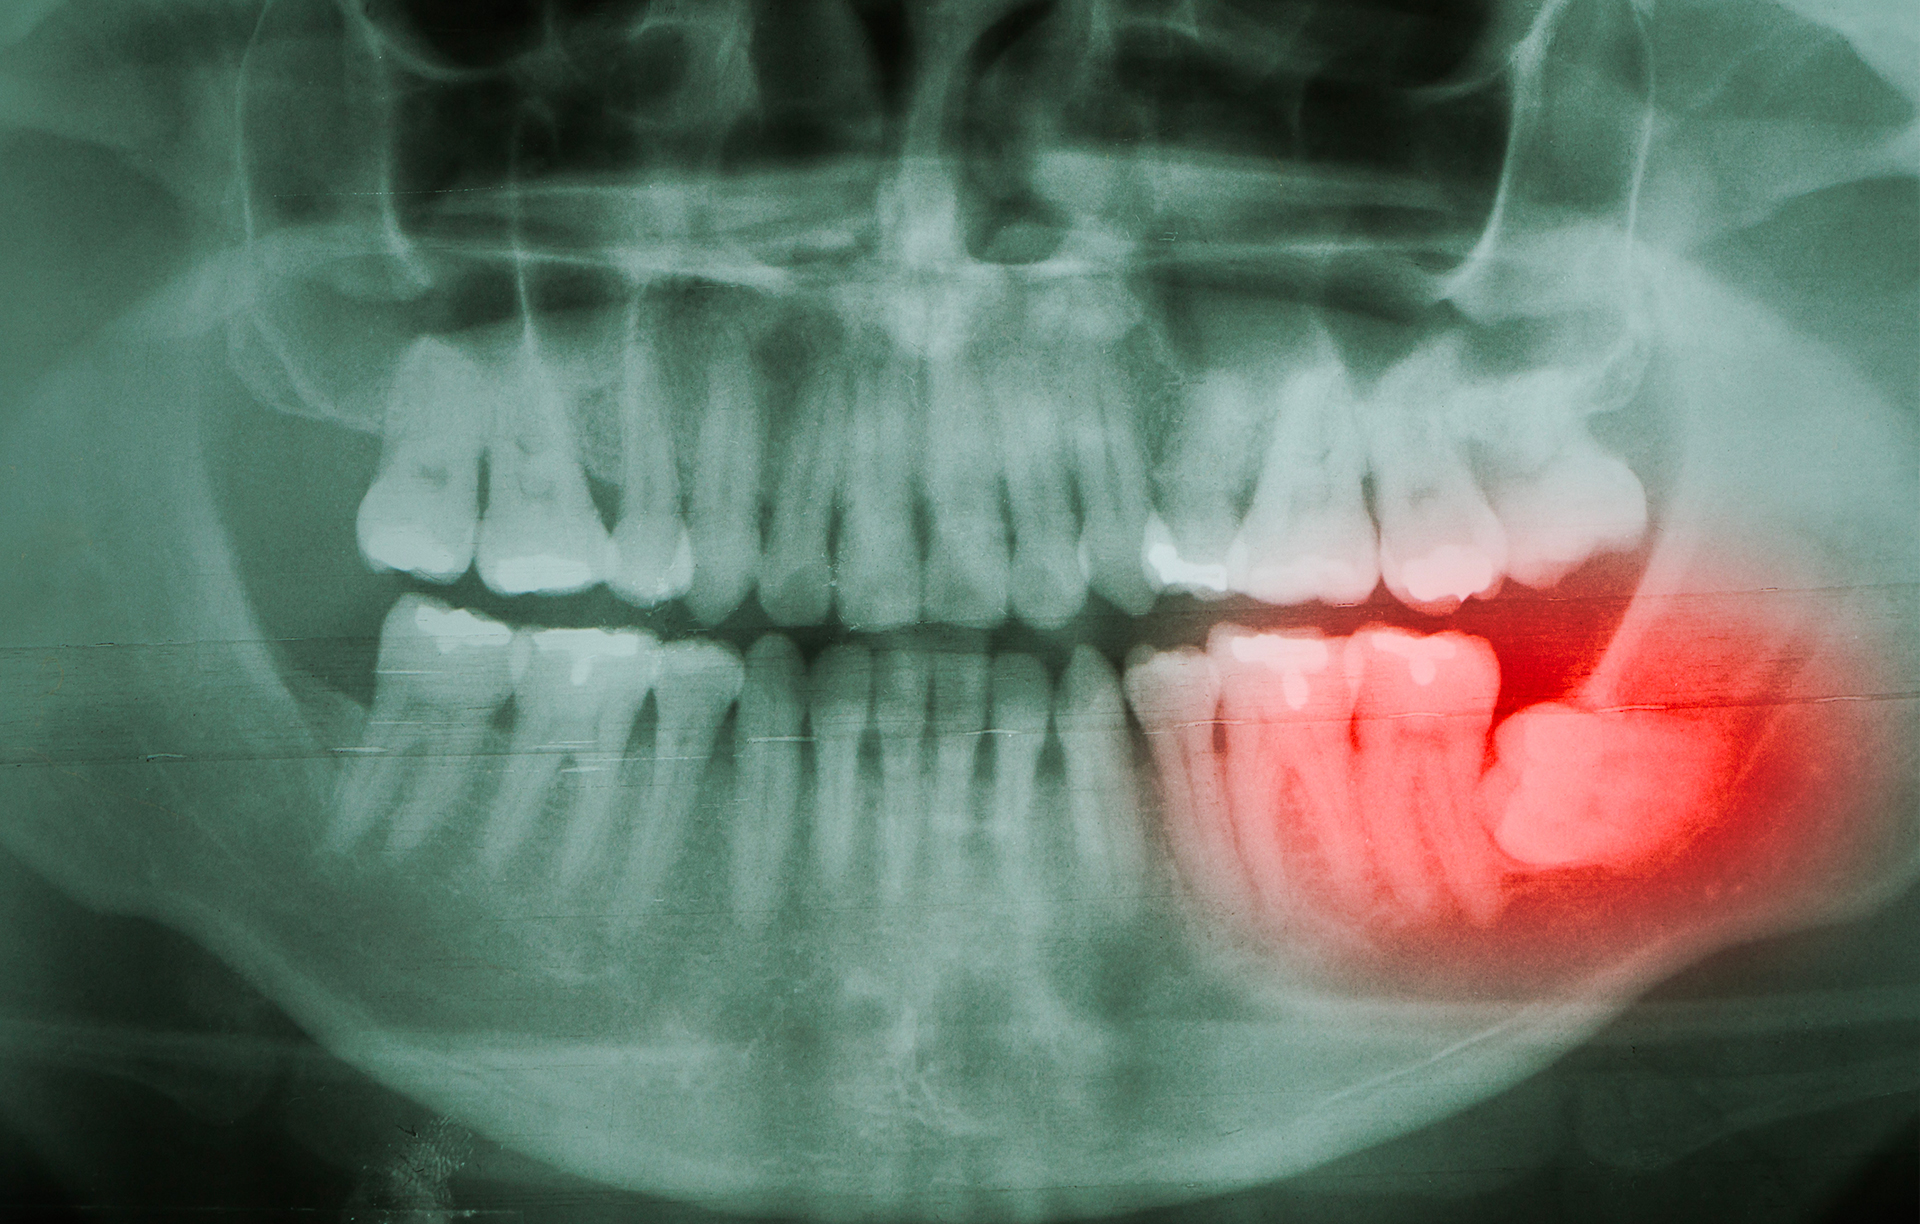

Wisdom teeth extraction

The prophylactic extraction of wisdom teeth during an orthodontic treatment, the extraction of an ectopic dental inclusion and an extraction in a pathological context (cyst, tumour, abscess) all require the expertise of a maxillofacial surgeon in order to avoid major sequelae.